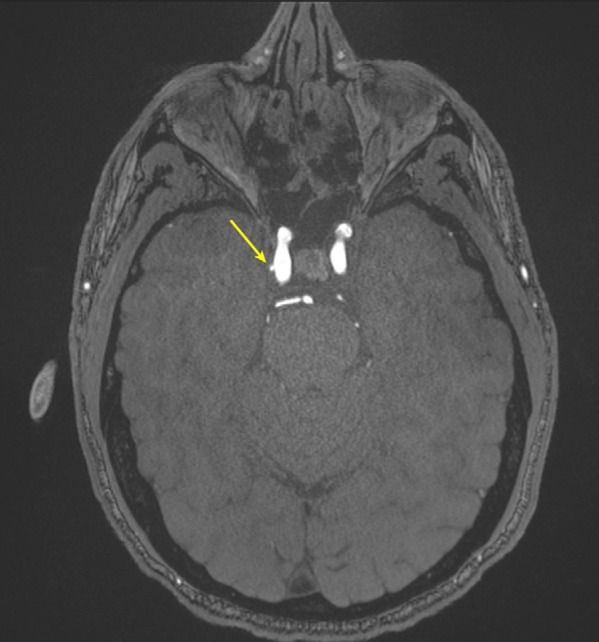

A Brazilian man died January 16 after bringing a concealed gun into the room where his mother was to undergo an MRI exam, according to a February New York Post report.

Leandro Mathia de Novaes, a lawyer, brought a registered, licensed personal handgun into the MRI exam room at the Laboratorio Cura in São Paulo. The MRI's magnetic field caused the gun to fire into de Novaes' abdomen; he was taken to a hospital but died on February 6.

The facility stressed that it had "followed all accident prevention protocols," the Post report noted.

"Both the patient and his companion were properly instructed regarding the procedures for accessing the examination room and warned about the removal of any and all metallic objects," Laboratorio Cura said in a statement.

Magnet-related MRI accidents are rare, but do happen: In 2018, a man from Mumbai, India, died after bringing an oxygen tank into the scanner suite; in 2020 a Swedish nurse who wore a weighted vest into the MRI room was injured; and in 2021, a South Korean man was killed by an oxygen cylinder brought into the MRI suite.